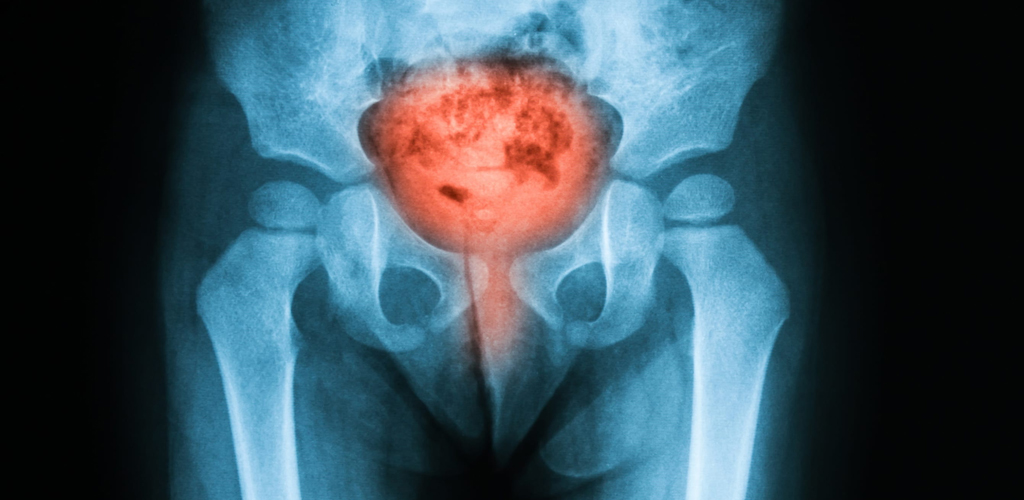

Os tipos de câncer mais frequentes que acometem o sistema urológico são: próstata, bexiga e rim. Eles são responsáveis por mais da metade dos casos